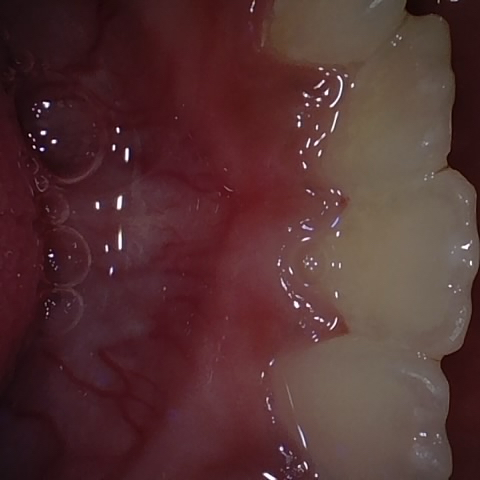

NHD25463

Annotated as "Good"

Original Image Rendering Image